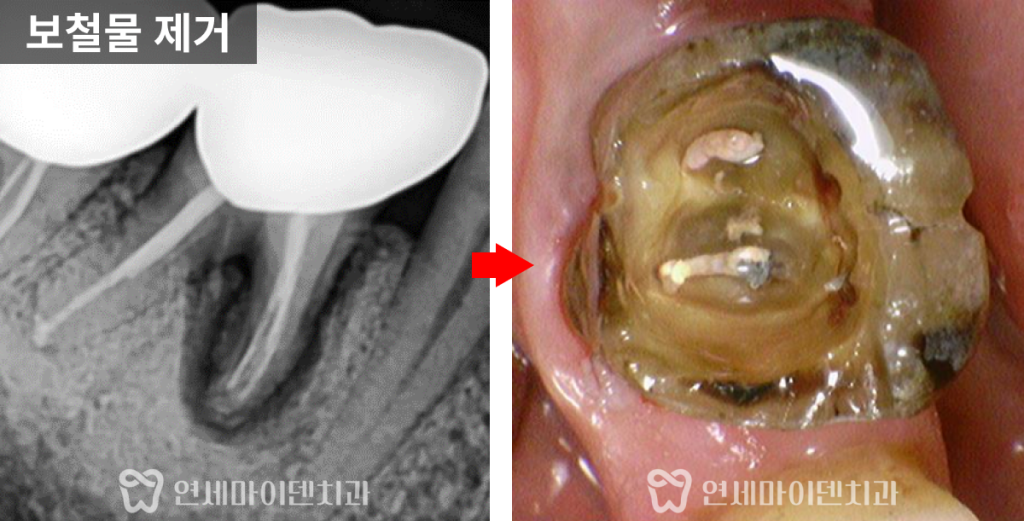

보철물을 제거하고 내부를 확인했을 때,

육안으로는 금이 보이지 않았습니다.

그러나 녹아 있는 뼈의 양상을 볼 때

치근 쪽 크랙 가능성이 높았습니다.

그래서 잇몸을 조금 열어서

내부를 직접 들여다보는 과정을 거쳤습니다.

결과적으로 뿌리에서 올라오는

수직치근파절(크랙 치아)이 확실히 확인되었습니다.

치관 쪽까지 금이 간 경우에는

육안이나 미세현미경으로 크랙을 확인할 수 있지만,

뿌리에서 올라오는 금은 치아 표면을

미세현미경으로 봐도 확인이 잘 안되는 경우가 많습니다.

이 환자분도 치아 뿌리쪽부터 올라오는 크랙이라

겉으로 확인이 되지 않았습니다.